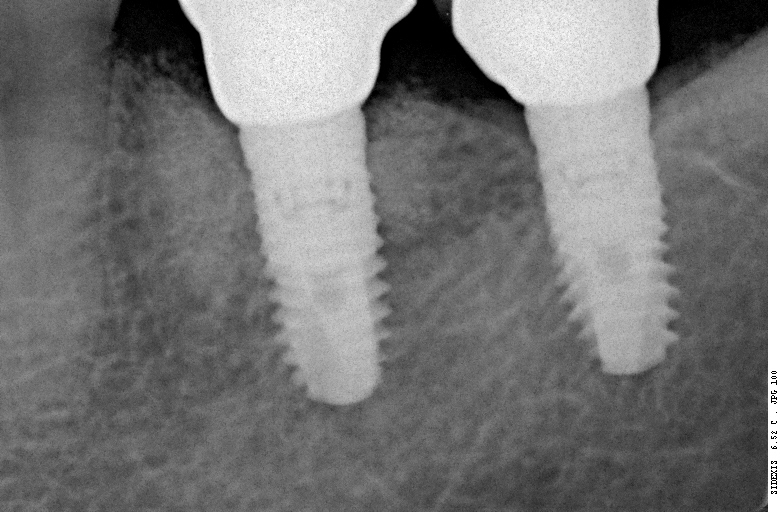

В хирургической практике я использую прицельные снимки как для первичной диагностики: например, чтобы быстро понять локализацию ретинированного зуба мудрости и его отношение к окружающим структурам, либо для интра- и послеоперационного контроля результатов имплантологического лечения. А наличие цифровой базы радиовизиографических снимков позволяет понять, как ведет себя протез на импланте в течение длительного времени:

Наиболее важным исследованием для имплантологии и хирургии является компьютерная томография. Именно с помощью нее мы досконально изучаем костную ткань в области операции, определяем ее конфигурацию и структуру, планируем размер и положение импланта в челюстной кости:

Конечно, существуют доктора, которые игнорируют важность компьютерной томографии для имплантации, но нужно помнить, что в этом случае очень высока вероятность ошибки. А в такой сфере как хирургия, ошибки не очень желательны, верно?

Я работаю со всеми существующими программами дентальных томографов. Изучение снимка, его описание и все измерения всегда провожу самостоятельно. Идеальный вариант — изначальный снимок на диске, без распечаток, измерений и описаний.